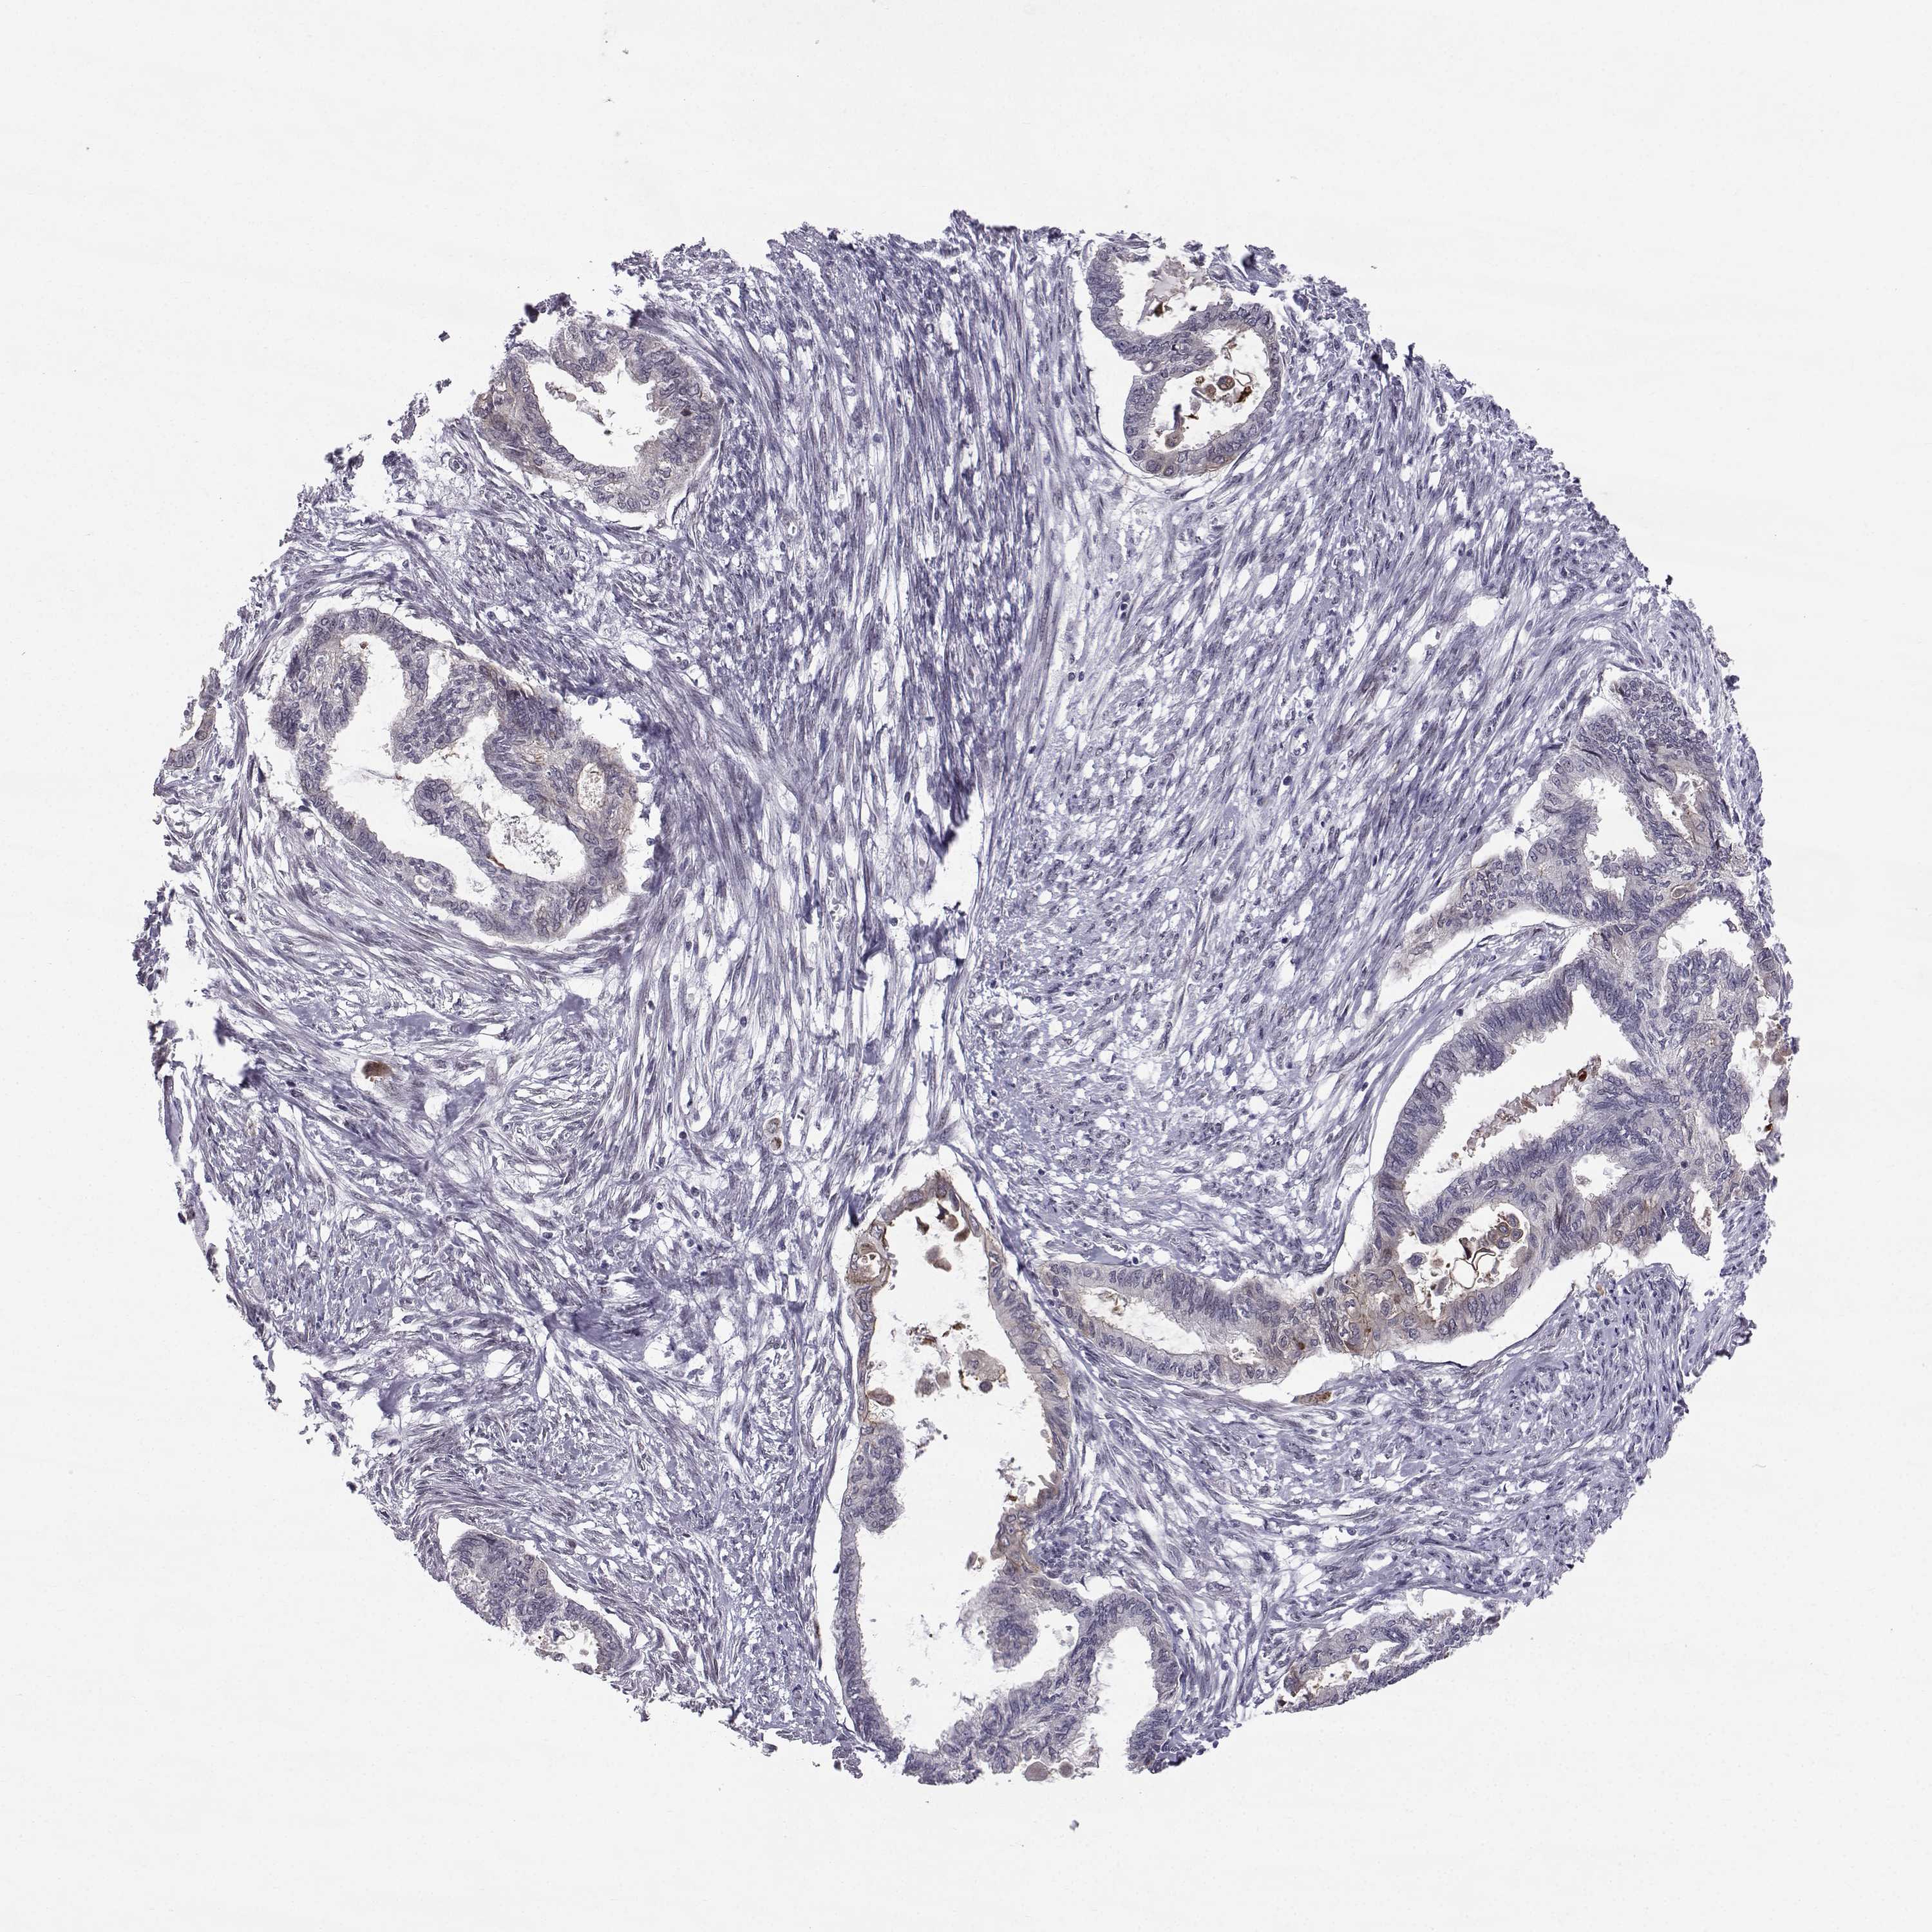

ENDOMETRIAL CANCER - Protein expressioni

A mouse-over function shows sample information and annotation data. Click on an image to view it in a full screen mode. Samples can be filtered based on level of antibody staining by selecting one or several of the following categories: high, medium, low and not detected. The assay and annotation is described here.

Note that samples used for immunohistochemistry by the Human Protein Atlas do not correspond to samples in the TCGA dataset.

Antibody stainingi

Antibody staining in the annotated cell types in the current human tissue is reported as not detected, low, medium, or high, based on conventional immunohistochemistry profiling in selected tissues. This score is based on the combination of the staining intensity and fraction of stained cells.

Each image is clickable and will lead to virtual microscopy that enables deeper exploration of all samples and also displays staining intensity scores, fraction scores and subcellular localization as well as patient and tissue information for each sample.

Antibody HPA066927

Staining

High

Medium

Low

Not detected

Intensity

Strong

Moderate

Weak

Negative

Quantity

>75%

75%-25%

<25%

None

Location

Nuclear

Cytoplasmic/membranous

Cytoplasmic/membranous,nuclear

Adenocarcinoma, NOS